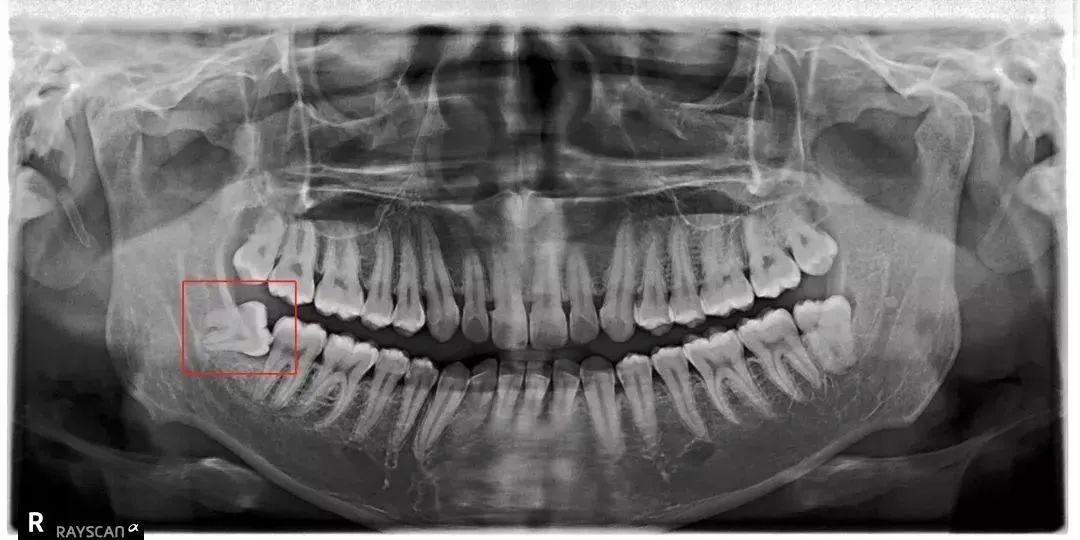

请牙医帮我看看这个x片,我这个智齿和埋伏牙该拔吗?哪颗拔掉呢.

x光片可以看到智齿是埋伏阻生的,属于有一定复杂程度的,今天在北京